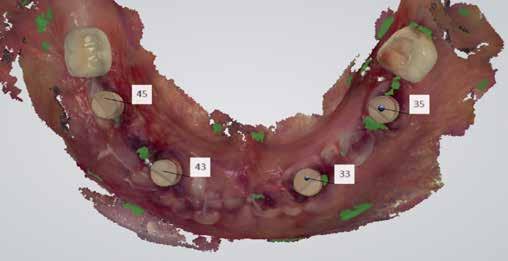

A fogakat virtuálisan eltávolítottuk a 3shape Implant Studio szoftver segítségével, a 3.7 és 4.7 korona-pótlásokat meghagytuk. Ezek a koronák referencia területekként, stabilizáló támasztékként fognak funkcionálni a sebészeti fúrósablonhoz. A hátsó koronák megtartásával megtartottuk az okklúziót és az okklúzió vertikális dimenzióját (VDO), (7-8. kép).

A nagy fesztávú híd szétvágása a megmaradt fogak eltávolítása előtt (14. kép). Implantációs sebészeti fúrósablon a teljes tisztázás és a csontmaradványok redukálását követően.

Rögtön a sebészeti eljárást követően a BioHorizons szkennelő fejeket felpattintottuk, és a lágy szövetek zárását követően megtörtént a 3shape digitális intraorális lenyomatvétel. Pontosabbnak tartom ezt a változatot, mint a fogpótlás és az implantátumok egyidejű tervezését. Vannak olyan tűréshatárok, amelyek befolyásolhatják a paszszív illeszkedést több implantátum használatának esetében (17. kép).

Az okklúzió és a szkennelő fejek háromdimenziós térbeli környezetben történő beszkennelésének képessége lehetővé teszi, hogy ez a munkafolyamat sokkal pontosabb és időtakarékosabb legyen az analóg munkavégzésnél (18-20. kép).

18-20. kép: 3shape intraorális szken felvételek a sebészetet követően.